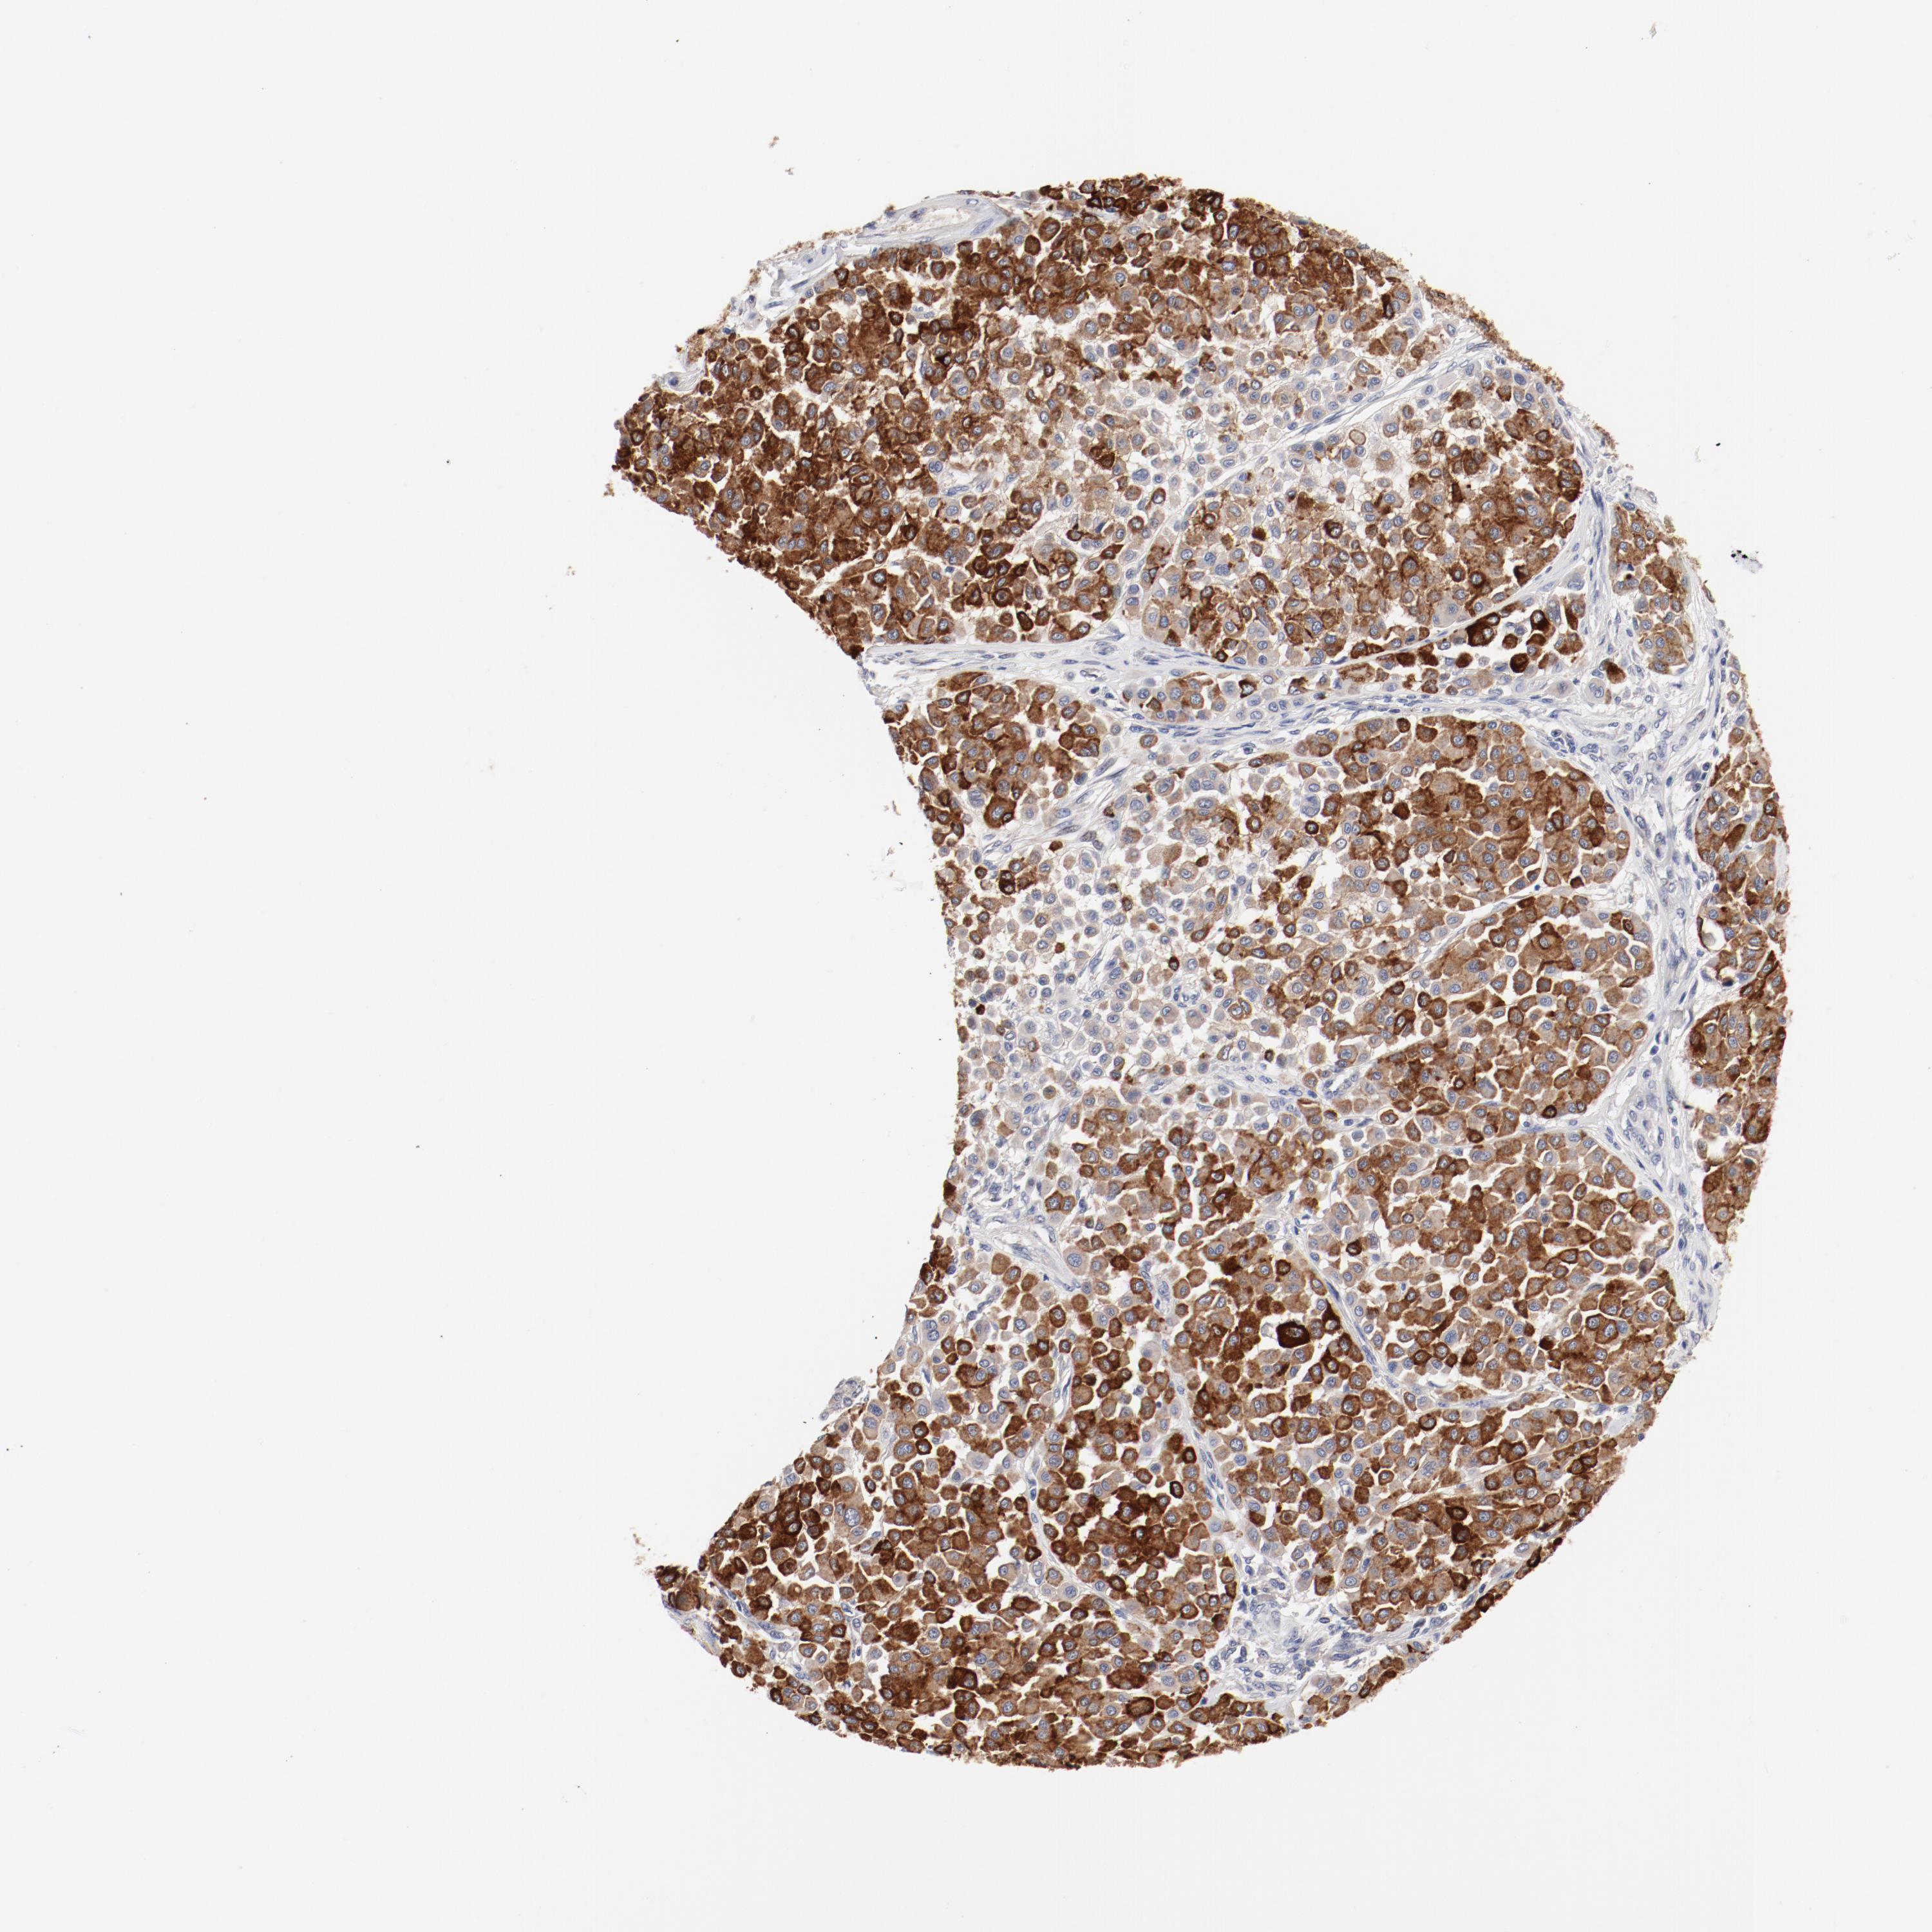

MELANOMA - Protein expressioni

A mouse-over function shows sample information and annotation data. Click on an image to view it in a full screen mode. Samples can be filtered based on level of antibody staining by selecting one or several of the following categories: high, medium, low and not detected. The assay and annotation is described here.

Note that samples used for immunohistochemistry by the Human Protein Atlas do not correspond to samples in the TCGA dataset.

Antibody stainingi

Antibody staining in the annotated cell types in the current human tissue is reported as not detected, low, medium, or high, based on conventional immunohistochemistry profiling in selected tissues. This score is based on the combination of the staining intensity and fraction of stained cells.

Each image is clickable and will lead to virtual microscopy that enables deeper exploration of all samples and also displays staining intensity scores, fraction scores and subcellular localization as well as patient and tissue information for each sample.

Antibody HPA003648

Staining

High

Medium

Low

Not detected

Intensity

Strong

Moderate

Weak

Negative

Quantity

>75%

75%-25%

<25%

None

Location

Nuclear

Cytoplasmic/membranous

Cytoplasmic/membranous,nuclear

Malignant melanoma, NOS